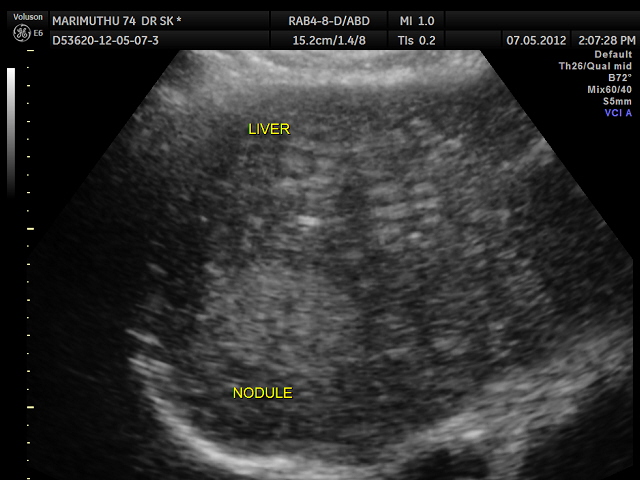

Please note that the ultrasound pictures of this patient are from our records. The PET CT images are done elsewhere at Chennai. They are reproduced here as they give the full picture of the clinical presentation.

This 74 year old gentleman has been coming to me for more than 10 years for mild systemic hypertension and hypothyroidism.He used to smoke cigars until a few years ago. 3 years ago he developed unexplained giddiness and on evaluation was found to have pituitary macroadenoma. Endocrine and neuro surgical consulatations were sought and he was on cabergoline and was doing very well. In April 2012 , he came for a routine review and was asked to continue his existing medications . One week later he came again with severe right upper quadrant pain and aversion to food. There was no history of cough in the recent past. He was advised an ultrasound scan of the abdomen and the findings are as below.

Extensive FDG avid hepatic metastases involving both lobes.